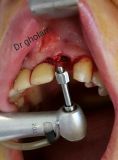

معرفی سیستم SPI همراه با جراحی زنده و Immediate Loading - آبان ۹۵

جراح وسخنران : استاد دکتر غلامعلی غلامی